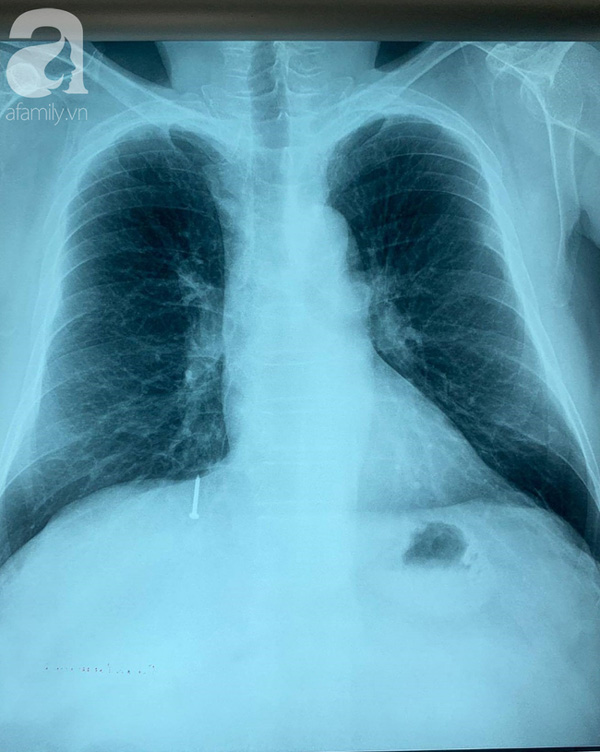

Ảnh chụp X-quang khiến các bác sĩ lầm tưởng dị vật vào đường tiêu hóa.

Nhưng sự thật dị vật đã rơi vào phổi.

Tại bệnh viện tuyến tỉnh, khi chụp X-quang, các bác sĩ nghi dị vật đã đi từ dạ dày xuống ruột. Tuy nhiên khi chuyển lên Bệnh viện Chợ Rẫy (TP.HCM), qua hình ảnh CT-scan kíp trực lại phát hiện chiếc đinh đã vào phổi.